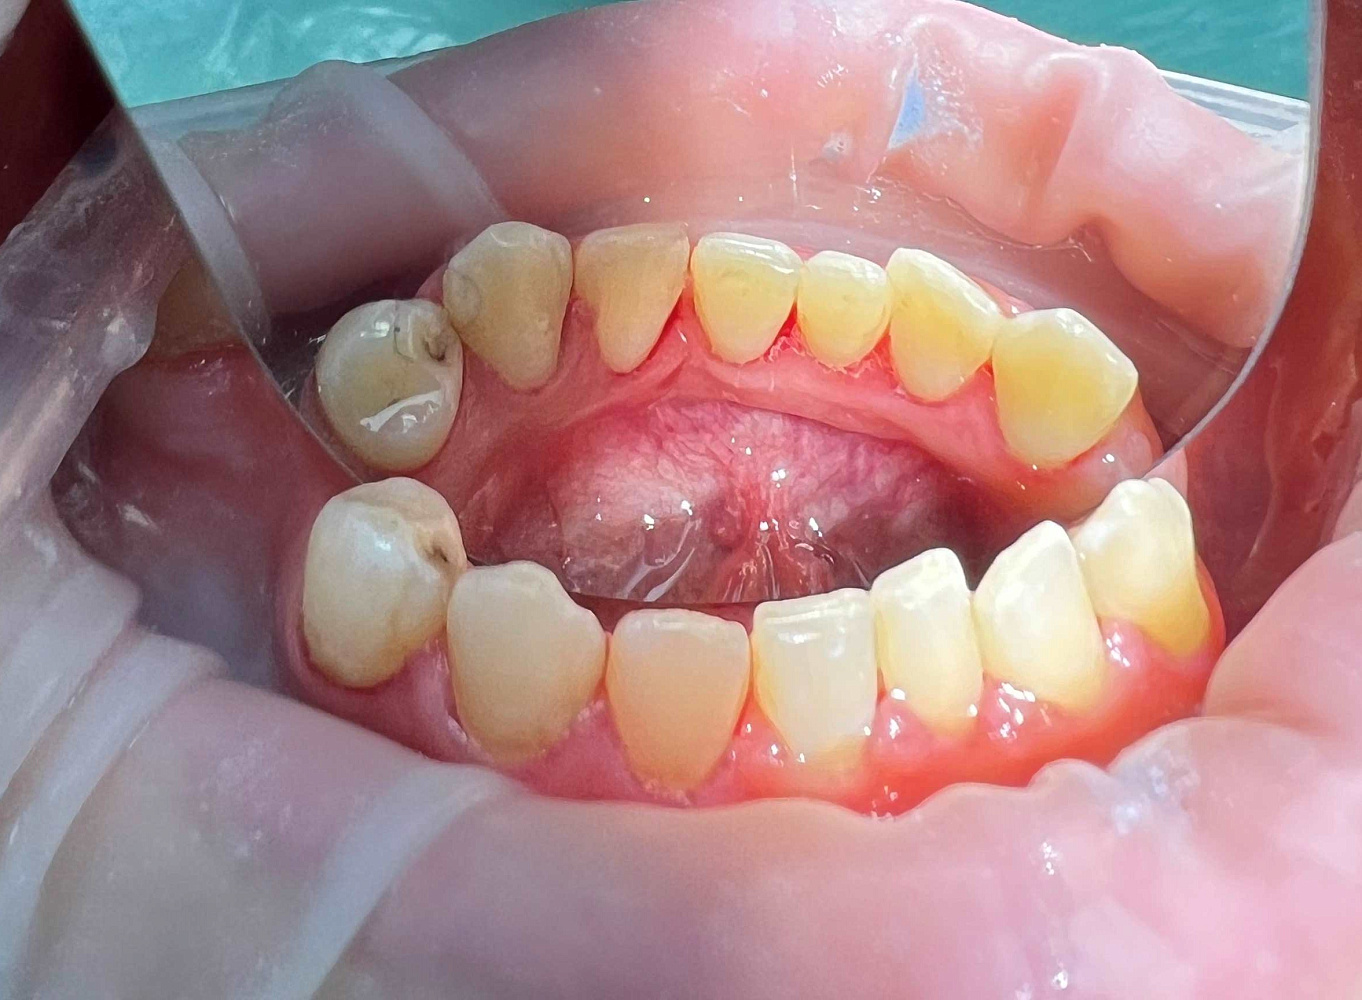

Профессиональная гигиена полости рта — это комплексная профилактическая процедура, направленная на удаление зубных отложений и поддержание здоровья дёсен. Во время процедуры врач последовательно очищает поверхность зубов от твёрдых и мягких отложений, снижая риск кариеса, воспаления дёсен и неприятного запаха изо рта. Профессиональная гигиена проводится с использованием современных методик и подходит пациентам любого возраста как самостоятельная профилактика, так и подготовка к лечению.

Регулярная профессиональная гигиена полости рта позволяет поддерживать чистоту зубов в тех зонах, которые недоступны для домашнего ухода. После удаления камня и налёта поверхность зубов становится более гладкой, что замедляет повторное образование отложений. Завершающее фторирование снижает чувствительность эмали и повышает её устойчивость к кариесу. Процедура рекомендована как профилактическая мера, а также перед отбеливанием, ортопедическим и терапевтическим лечением. Проведение профессиональной гигиены помогает сохранить здоровье зубов и дёсен, улучшить внешний вид улыбки и продлить результат последующего стоматологического лечения.